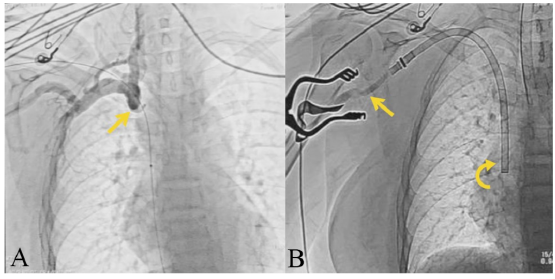

El dispositivo HeRO® es una opción para el acceso de hemodiálisis en el paciente con oclusión de la vena central y puede ser en algunas ocasiones la única alternativa a la dependencia del catéter [11] (figura 3A y 3B).

Notas aclaratorias: para la figura 3B: el injerto anastomosado a la arteria braquial (flecha recta) y el componente de flujo venoso con extremo distal en la aurícula derecha a través de la vena yugular interna (flecha curva).

Figura 3 A. Cavografía que demuestra oclusión crónica de vena cava superior (flecha) y B. imagen de fluoroscopia que muestra los dos componentes del injerto HeRo®

Notas aclaratorias: el injerto que se anastomosará a la arteria braquial (flechas rectas), tunelizado por el tejido celular subcutáneo del brazo (punteado) y el componente de flujo venoso con acceso percutáneo en el cuello a través de la vena yugular interna (flecha curva).